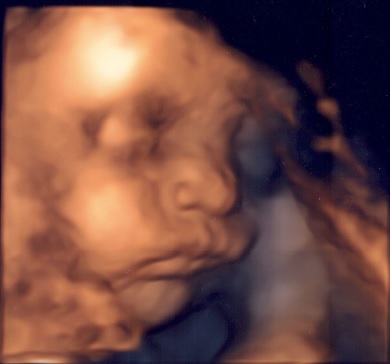

Ve středu jsem byla s přítelem na 3D utz a bylo to super, i když malej moc nespolupracoval. Paní doktorka se sice snažila, ale ho nic nerozhodilo, zkrátka pohodář. Potřetí potvrzený kluk i s fotografickým důkazem.

Co se týče měření, tak mě doktorka moc nepotěšila: začalo to tím, že hlavička je velká, holení kost je rovněž poměrně velká, bříško nám to naštěstí trochu srazilo, nicméně i tak máme přes 1 kg a nakonec to shrnula slovy, že prcek to určitě nebude

Je sice pravdou, že já i brácha jsme měli oba přes 4 kg, ale přesto jsem doufala v něco menšího. No uvidíme třeba už tolik neporoste

Každopádně připojuji fotečku :-)